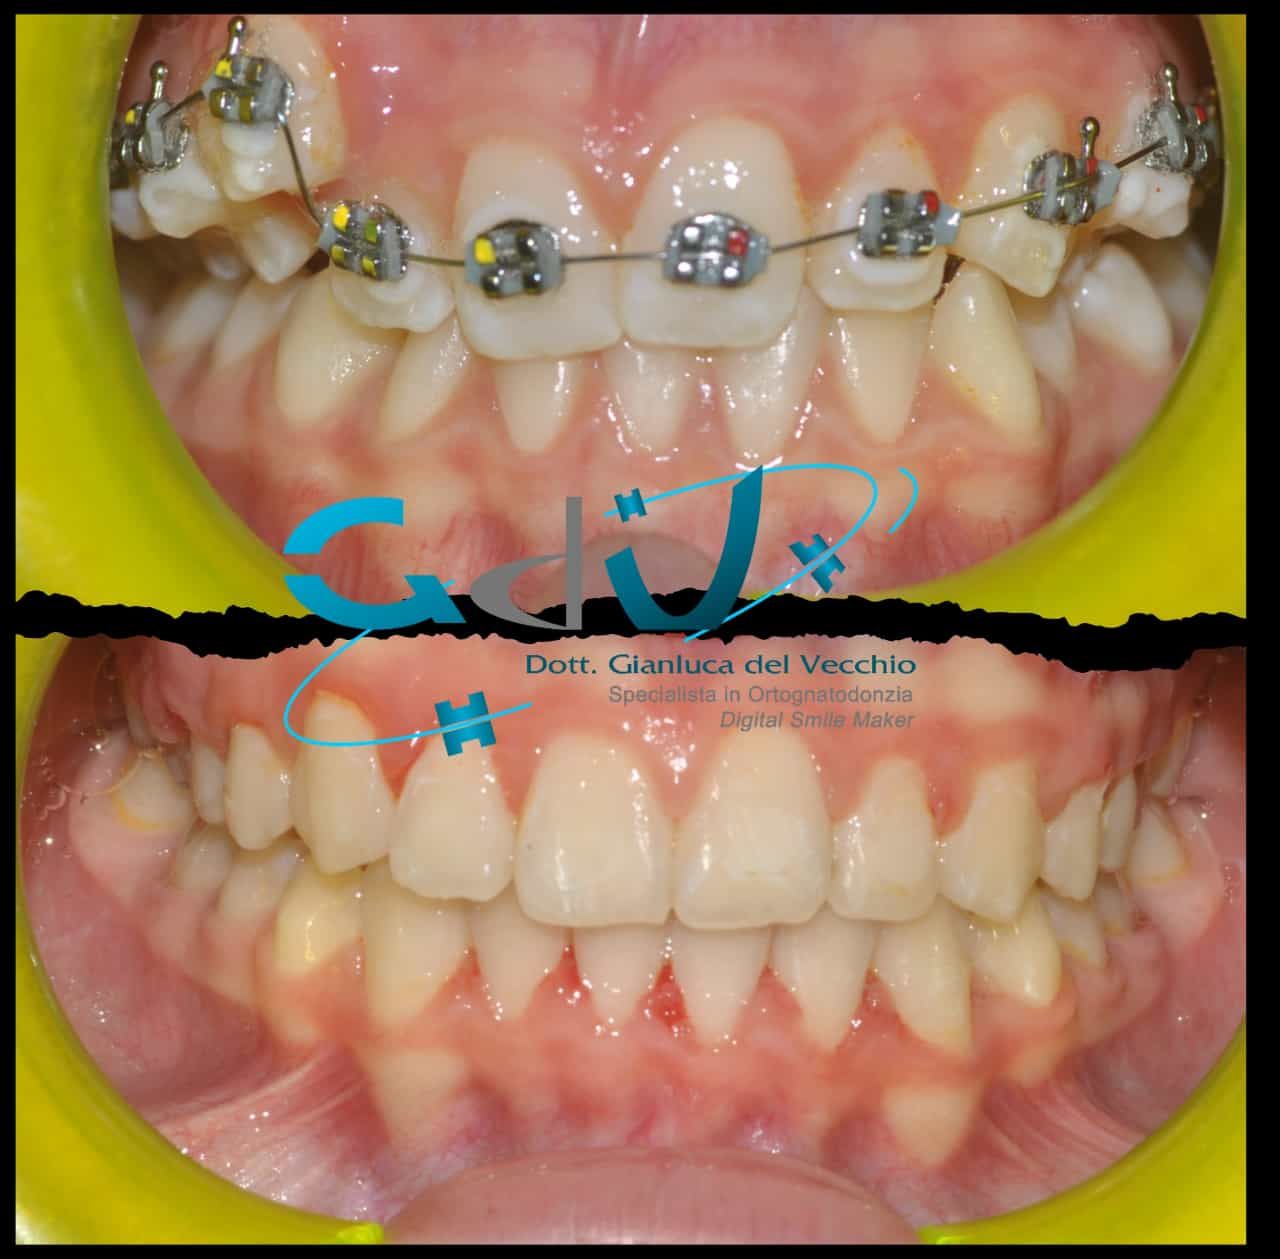

Il dottore ha acquisito una concezione quanto più pratica e moderna della disciplina e utilizza apparecchietti di diversi colori di tipo mobile e fisso, ma anche terapie sia estetiche che invisibili, fiore all’occhiello di poche realtà in Italia. Per terapie estetiche e invisibili si intendono quelle in grado di spostare i denti, senza che traspaia nulla dalla bocca o con stelline e fili bianchi, esattamente come i denti del paziente.

Ma ancora di più l’équipe è in grado di offrire un servizio davvero unico: la tecnica dei retainer attivi. Questa consiste in fili o bottoni che si incollano dietro i denti e che, quindi, nascondono completamente la terapia. Questo tipo di prestazioni aiuta a superare la grande difficoltà psicologica, che spesso si insinua anche negli adulti, di dover spostare i propri denti per un sorriso perfetto: si consideri che tale difficoltà non viene affrontata, il più delle volte, proprio per l’imbarazzo che una apparecchiatura ortodontica genera in chi la usa. Queste tecniche, insieme alle mascherine invisalign invisibili di cui è provider ufficiale e agli attacchi in ceramica, sono tutte quotidianamente utilizzate presso i nostri reparti, in cui è possibile associarle in un discorso multidisciplinare a tutte le altre esigenze della odontoiatria classica.